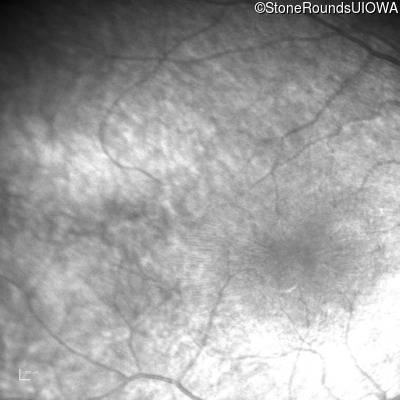

Infrared Fundus Photograph - Right - No Light Perception

Exemplar